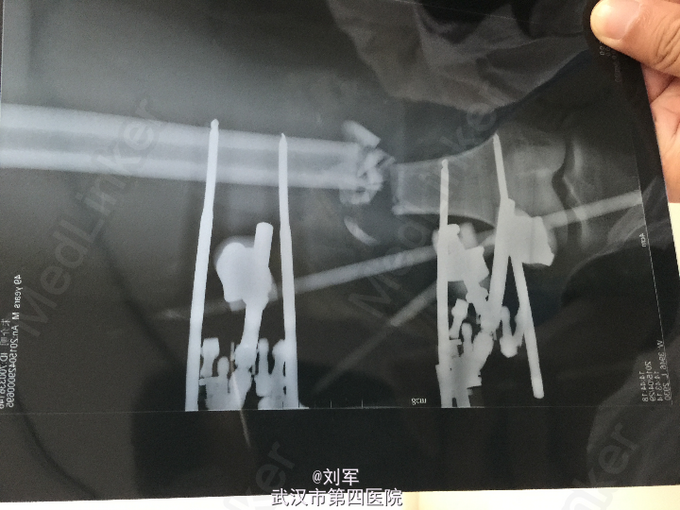

入院后,申请血液,急查左下肢动脉彩超:左侧股动脉下段断裂、栓塞。急诊麻醉下行清创+大隐静脉移植修复股动脉术+股骨复位外固定架固定术。

股动脉损伤为骨科临床较为棘手的急症,合并股骨开放性骨折、大腿肌群断裂时,急诊手术积极抢救休克、修复股动脉、固定骨折。